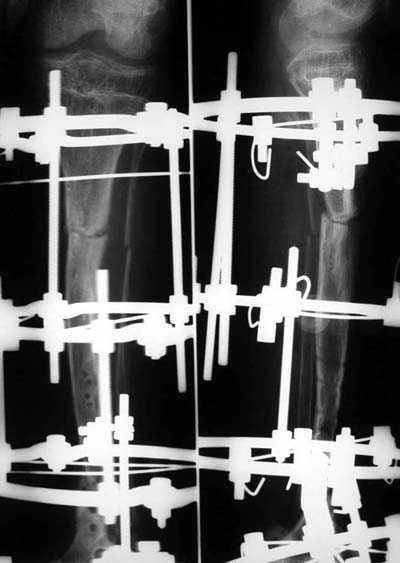

Уважаемые коллеги! В отделении на лечении наблюдается пациент 16 лет с диагнозом: Псевдоартроз костей левой голенив нижней трети. Вальгусная деформация обоих коленных суставов. Укорочение левой н/конечности11см. С 1997 года состоит на учёте у онколога с диагнозом: Рабдомиосаркома мышц тазового дна IV ст., с метастазами в метафизы берцовых костей.Проведена полихимиотерапия, лучевая терапия. В 1998 г. удаление опухоли. Послеоперационный период без особенностей. С 1998 года со стороны онкологии ремиссия, перестройка очагов метастазирования в берцовых костях по типу фиброзной дисплазии.В 1999 г. патологический перелом костей левой голени в н/трети. Лечение в гипсе 1.5 месяца, затем компрессионно-дистракционный остеосинтез апп. Илизарова. Сращения на месте псевдоартроза не достигнуто. С 1999г. ходит без нагрузки на левую н/конечность. Выраженный остеопороз костей н/конечностей. 17.11.05. Операция: Костная пластика зоны псевдоартроза левой б/берцовой кости по типу "русский замок", остеосинтез пластинкой и винтами. После начала нагрузки на конечность рецидив деформации, миграция фиксаторов. 05.12.06. Операция: Удаление фиксаторов из левой голени. Шарнирная остеотомия трети левой б/берцовой кости, остеотомия м/берцовой кости. Дистракционный остеосинтез апп. Илизарова. Устранены основные виды деформации б/берцовой кости. Планировали в дальнейшем несвободную костную аутопластику и интрамедуллярный остеосинтез с блокированием, но кость очень тонкая, склерозированная, выраженный остеопороз. Возникают большие сомнения о возможности сращения даже при этих условиях. Будем рады услышать ваши мнения по дальнейшему лечению данного пациента. Екатериан Анатольевна Озерова, детское отделение УНИИТО

А аппарат не демонтирован? Если так, то может быть попробовать такой вариант: провести две дополнителные спицы с напайкой в область формирующегося ложного сустава, предварительно подложив под напайки кортикальные пластины (аллотрансплантат) с перекрытием зоны псевдоартроза с двух сторон. Спицы с небольшим давлением. Также в эту зону уложить дименерализованный аллотрансплантат по типу "вязанки хвороста".